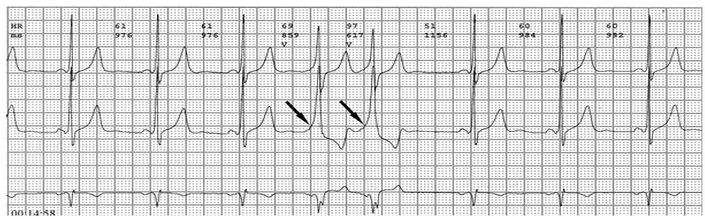

心电图检查及其特征

各旁路引起预激的心电图特征如下:

1、房室旁道

(1)PR间期(实质上是P-δ间期)缩短至0.12秒以下,大多为0.10秒;

(2)QRS时限延长达0.11秒以上;

(3)QRS波群起始部粗钝,与其余部分形成顿挫,即所谓预激;

(4)继发性ST-T波改变。

上述心电图改变尚有分为A、B两型的。A型的预激波和QRS波群在V1导联均向上,而B型V1导联的预激波和QRS波群的主波则均向下;前者提示左室或右室后底部心肌预激,而后者提示右室前侧壁心肌预肌。这种分类方法虽然受到预激是不同部位旁路所致的多变QRS波群的限制,但有助于区别旁路的心室端在左或右、前或后,因而沿用至今。

3、结室、束室连接

PR间期正常,QRS波群增宽,有预激波。预激综合征室上性心动过速发作时,预激表现大多消失,心电图表现为QRS波群形态正常的室上性心动过速。并发房扑或房颤时,QRS保持预激特征的不少见,心电图表现为QRS波群畸形宽大的房扑或房颤;心室率大多超过200次/分,甚至可达300次/分。房扑时可呈1:1房室传导,并可能辨认房扑波。房颤时心室律不规则,长间歇之后可见到个别QRS波群形态正常(可能为旁路不应期延长,房室结内隐匿传导作用消失后,冲动全部或大部经房室结传导所致),并可能辨认房颤波。心室率极快时,还可伴有频率依赖性心室内传导改变。